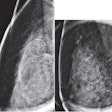

Early breast cancer was flagged by the CAD software three years prior to biopsy and showed a progressive increase in quantitative score over the three years. All images courtesy of Dr. Alyssa Watanabe.

Early breast cancer was flagged by the CAD software three years prior to biopsy and showed a progressive increase in quantitative score over the three years. All images courtesy of Dr. Alyssa Watanabe.In other results, the researchers found that progressive deep-learning training continued to improve the performance of the CAD software over time for breast masses.